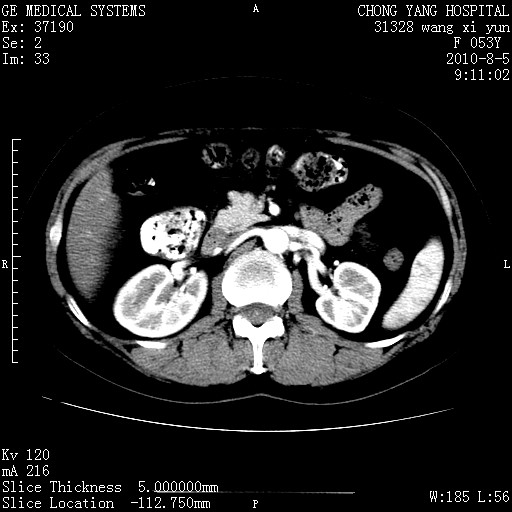

标题: CT28214:F41Y 血尿二十天,建议盆腔平扫加增强。

1)考虑肝左叶胆管细胞癌。2)脂肪肝。

支持胆管细胞ca。